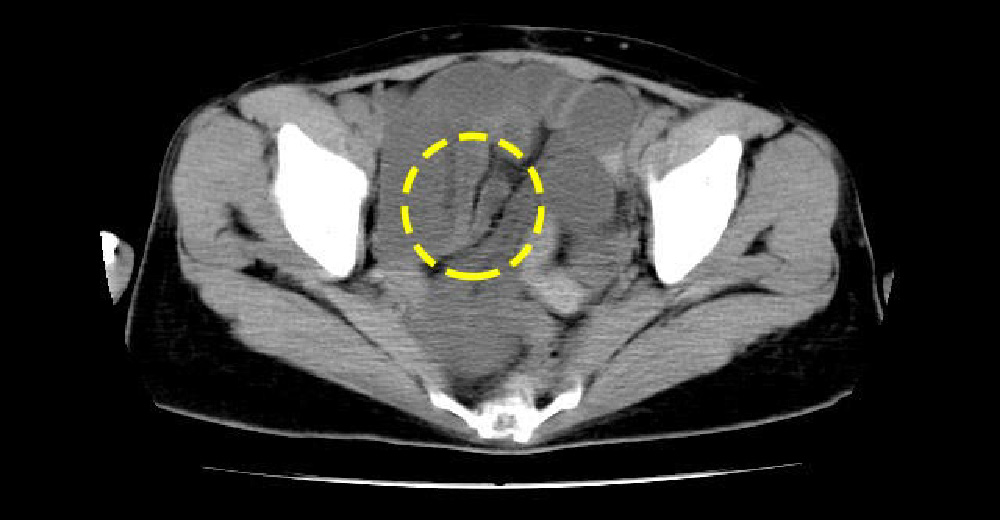

腸閉塞

原因は良性疾患から悪性のがんまで多岐にわたります。腹痛やお腹が張るなどの、典型的症状を訴えるかたは診断が容易なこともありますが、基本的にはCTを使用して診断することが多いです。場合によっては、緊急手術をしなければ命に関わることもあります。

腹痛で来院した症例です。過去の虫垂切除後、腹膜に小腸が癒着して屈曲しており、そのため腸管が拡張する腸閉塞に至っています。